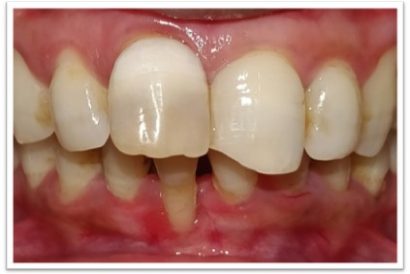

Patient Name: Sakshi Talwar

Tooth Number: 11

Diagnosis : fractured restoration

Treatment : Endodontic Treatment With 11 and fiber post and core, gingvectomy and frinectomy with 11

Restoration: Bonded Lithium Disilicate Emax Restoration